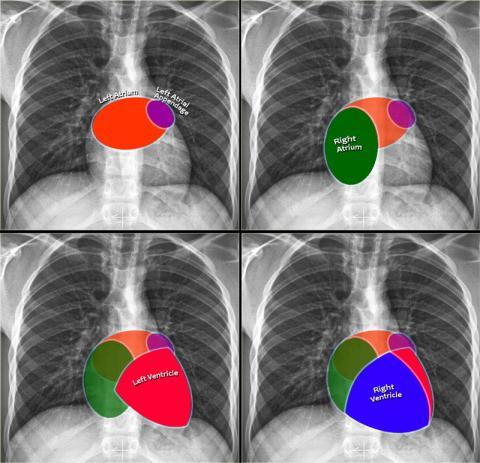

Heart borders on a CXR

How to identify pulmonary trunk on CXR?

ABove the left main bronchus but below the aortic knuckle